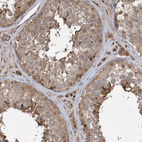

Immunohistochemical staining of human testis shows moderate cytoplasmic positivity in cells in seminiferous ducts.